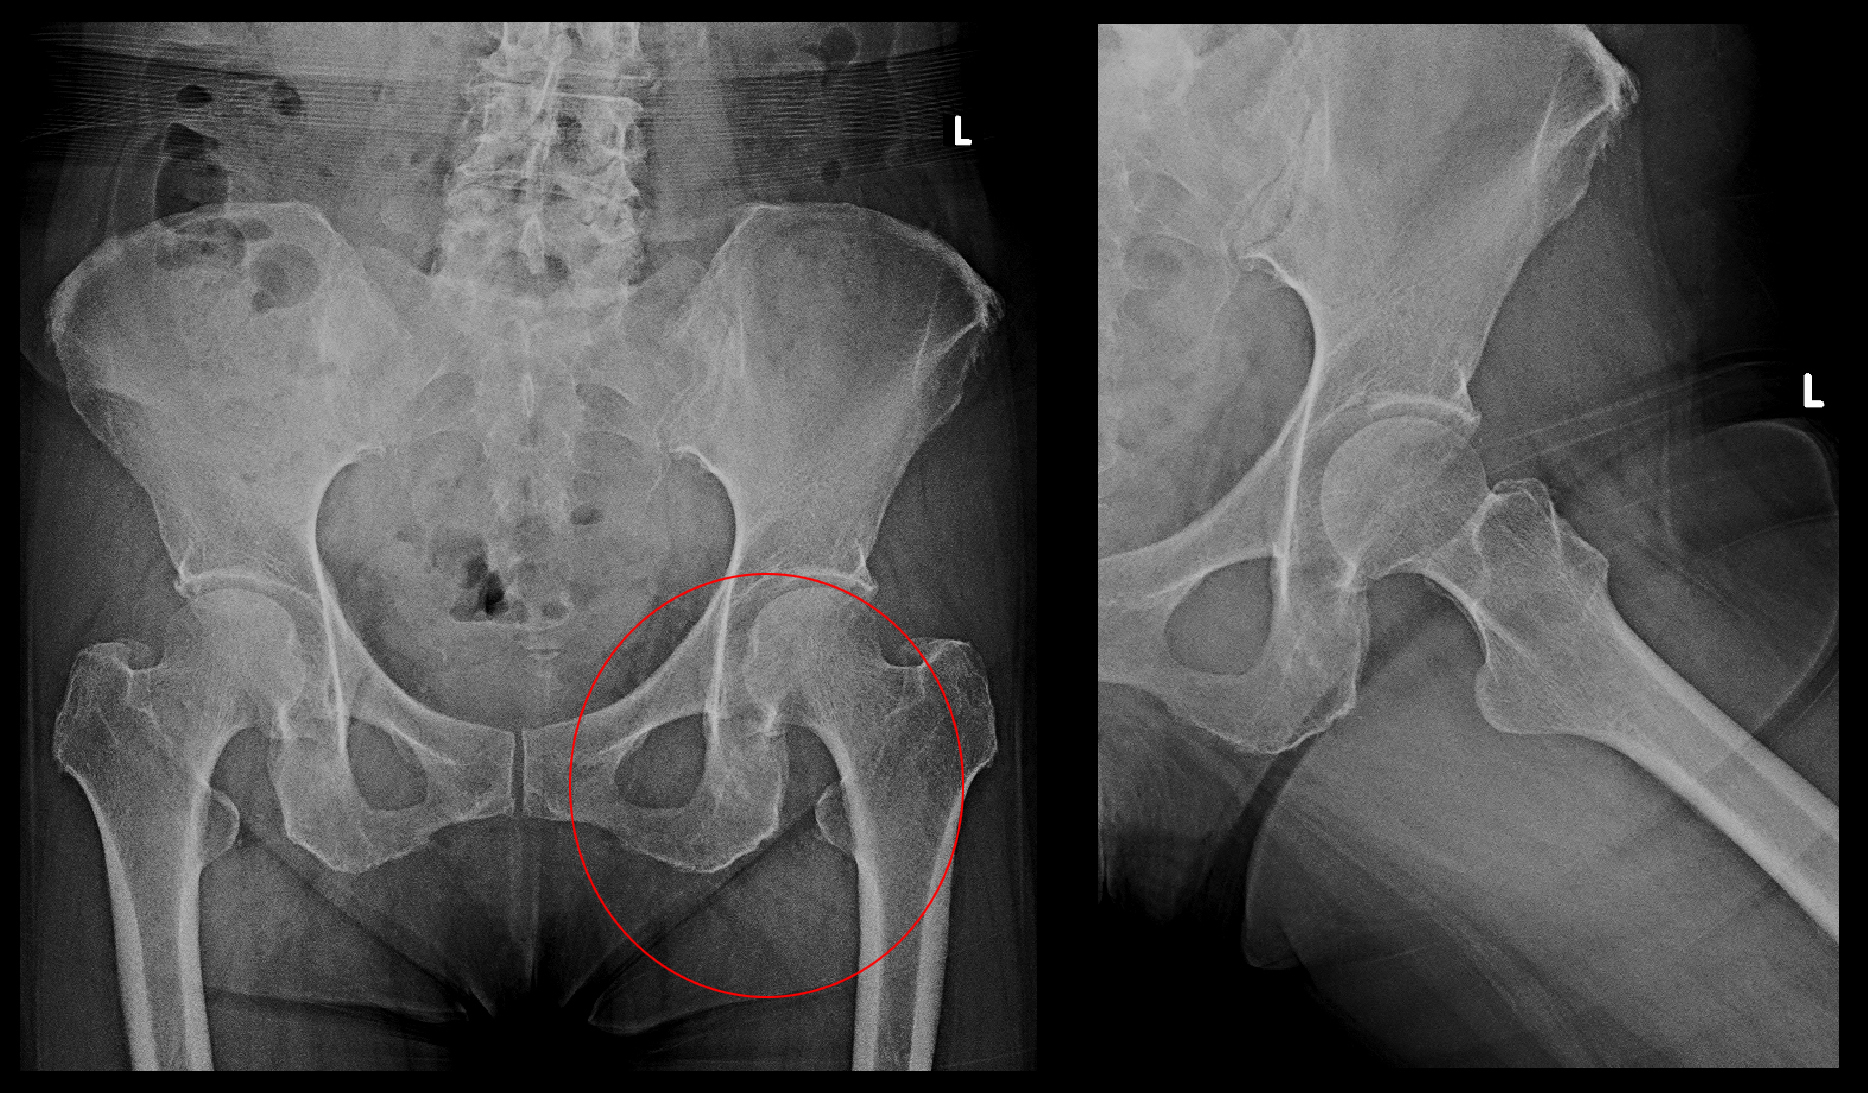

臀部痛・大腿部痛の患者さんでは股関節の異常の有無をチェックしますが、左股関節の異常を疑わせる理学所見がみられたため、股関節と腰椎のMRI検査を行いました。

赤丸が臀部痛の領域ですが、股関節のレントゲン像は異常はありません。

腰椎のMRI検査の所見は10か月前と変わりはありませんでしたが、股関節のMRI検査で左股関節周囲に広範な肉離れの所見(筋肉層の中に出血を示す白い所見)が確認されました。患者さんが10か月前と同じ腰に起因する痛みと感じても、その原因は全く別なものでした。